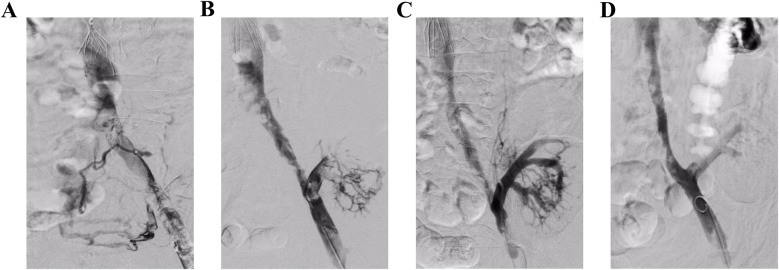

下肢深静脉血栓(DVT)合并移植肾静脉血栓形成是一种罕见而复杂的静脉血栓栓塞,可导致移植肾静脉阻塞。这种情况导致肾脏实质水肿,最终损害移植器官的功能。它是肾移植后的灾难性并发症,可能导致移植肾功能丧失和手术失败。治疗的主要目的是及时清除移植肾静脉中的血栓,从而尽快恢复正常的静脉回流和肾功能,提高患者预后。目前,手术取栓和溶栓治疗被认为是主要的治疗方式。外科取栓术通常被推荐为一线治疗方法,因为它能快速清除血栓。迄今为止,关于使用AngioJet取栓系统治疗DVT合并移植肾静脉血栓的文献有限。在此报告中,我们报告两例中年男性患者诊断为急性下肢深静脉血栓合并移植肾静脉血栓。两例患者分别在15年和4年前接受了异基因肾移植。在这些病例中,我们采用AngioJet取栓系统进行急诊血栓抽吸治疗。两例患者下肢深静脉及各自移植肾静脉内的血栓均被完全清除。随后,两例患者尿量逐渐增加;此外,肾功能逐渐改善到可接受的范围。值得注意的是,在随访评估中,患者均未出现术后并发症,也未出现血栓复发。

Lower extremity deep venous thrombosis (DVT) combined with transplanted renal vein thrombosis represents a rare and complex form of venous thromboembolism that leads to obstruction of the transplanted renal vein. This condition results in parenchymal edema of the kidney, ultimately impairing the function of the transplanted organ. It constitutes a catastrophic complication following renal transplantation, potentially resulting in loss of function of the transplanted kidney and failure of the surgical procedure. The primary objective of treatment is to promptly remove thrombi from the transplanted renal vein, thereby restoring normal venous return and renal function as swiftly as possible to enhance patient prognosis. Currently, surgical thrombectomy and thrombolytic therapy are considered the mainstay treatment modalities. Surgical thrombectomy is generally recommended as a first-line approach due to its efficacy in achieving rapid thrombus removal. To date, there exists limited literature regarding the utilization of the AngioJet thrombectomy system for managing DVT in conjunction with transplanted renal vein thrombosis. In this report, we present two cases involving middle-aged male patients diagnosed with acute lower extremity DVT complicated by transplanted renal vein thrombosis. Both patients had undergone allogeneic kidney transplantation 15 and 4 years prior, respectively. In these instances, we employed the AngioJet thrombectomy system for emergency thrombus aspiration treatment. The thrombi within both patients' lower extremity deep veins and their respective transplanted renal veins were completely removed. Subsequently, urine output gradually increased for both patients; moreover, their renal function progressively improved to an acceptable range. Notably, neither patient developed postoperative complications nor exhibited any recurrence of thrombi during follow-up evaluations.